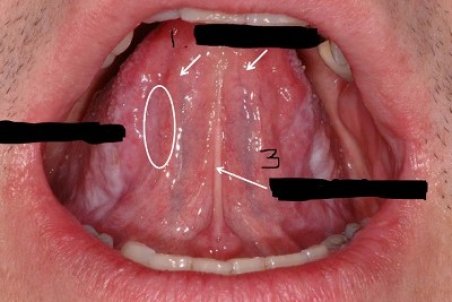

برامدگی و توده در زبان نشانه چیست؟

یک نوع از بیماری عفونی و یا کیست که در زیر زبان به صورت زائده های برجسته پدید می آید زائده های زیر زبانی گفته میشود که ممکن است باعث بروز بیماری های بدخیم شود.